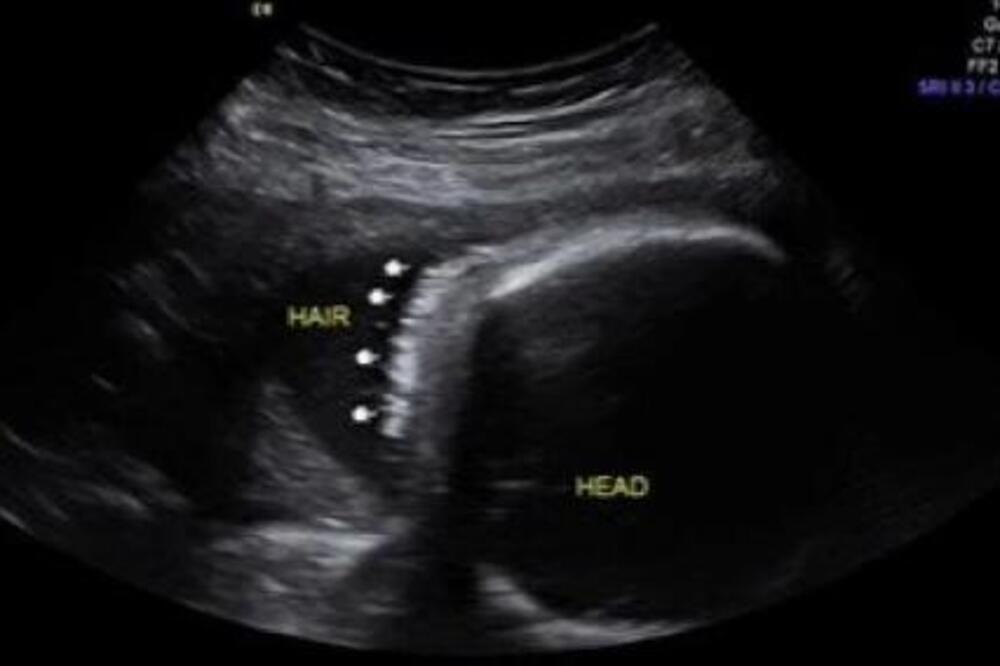

Džordan Filips je mama preslatke devojčice. Sve detalje napretka trudnoće, odlazak na preglede kao i sam porođaj, roditelji su podelili sa ljudima koji ih prate na društvenim mrežama. Oni su prošle godine išli na ultrazvuk kako bi pratili napredak devojčice. Pregled je bio zakazan 26. septembra 2023. godine. Tada su na ultrazvuku videli svoju devojčicu, ali i nešto drugo što im je privuklo pažnju.

Sliku sa ultrazvuka prikazali su i u videu na TikToku. Naime, devojčica je imala kosu koja je jasno bila obeležena strelicama. Nakon ovog videa, slede slike sa porođaja. Tek tada, kosa je zaista bila primetna i mnogi su bili oduševljeni kako je lepa, gusta i crna.

- Ova devojčica je zapravo rođena sa baš malo kose - napisala je ironično majka devojčice u opisu videa na TikToku.